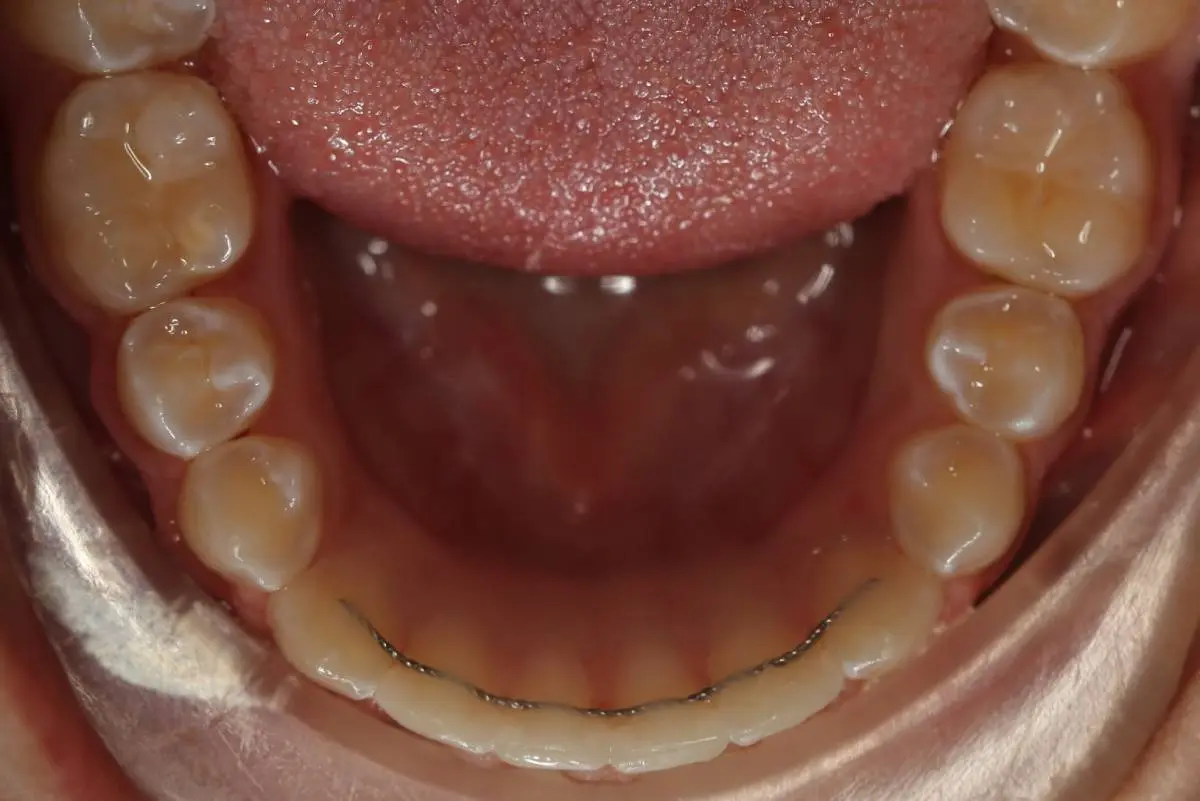

Fixed Retainers

Fixed retainers consist of a thin wire bonded to back surface of your six front teeth, so they are not visible. They are comfortable and with adequate brushing and flossing they do not cause tooth or gum disease. It is a permanent retainer as it cannot be removed on every day basis, but it may be removed by the orthodontist or dentist at any time if desired.